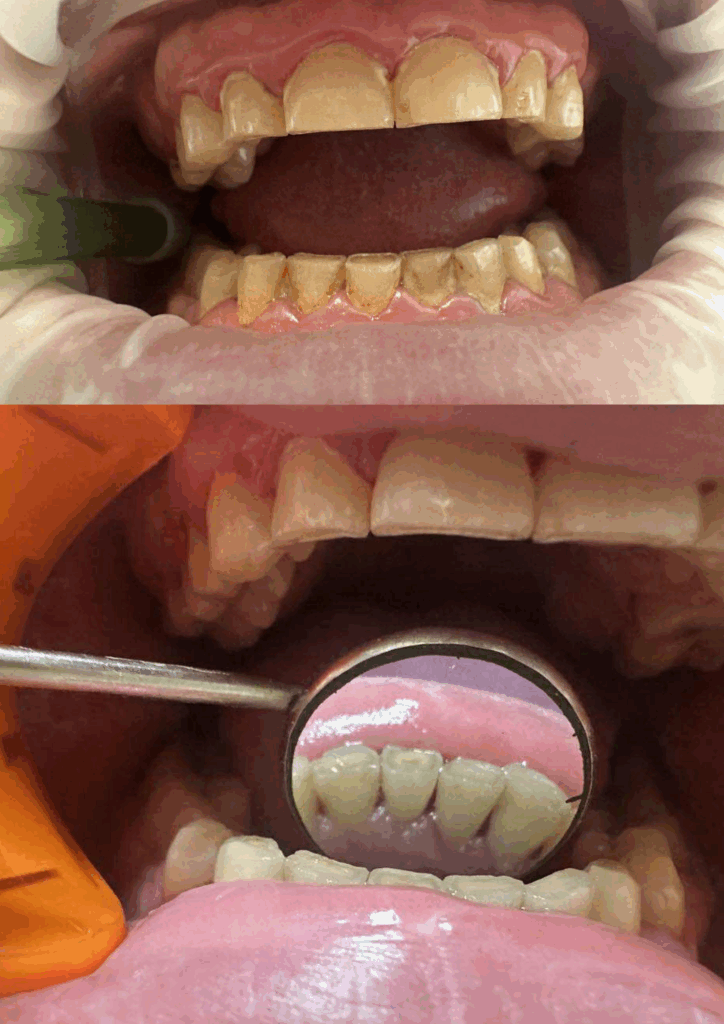

Zęby po wybielaniu, rozjaśnione o 2 tony.

Zęby wybielone o dwa tony, wyrównanie koloru z koronami porcelanowymi

Wybielanie zębów – efekt przed i po zabiegu

Wybielanie zębów metodą gabinetową – efekt przed i po